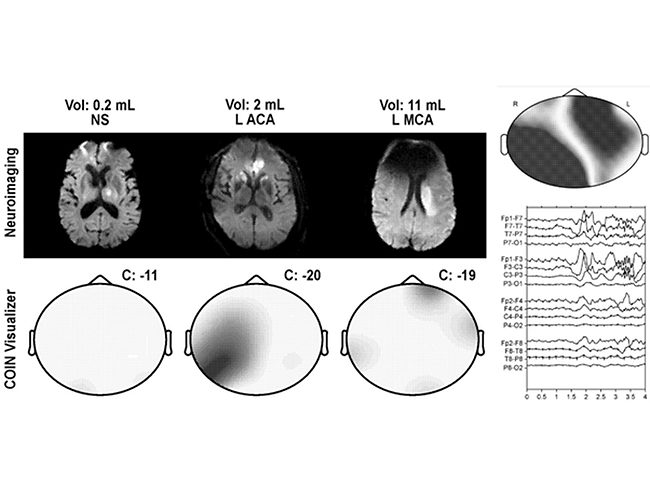

Quantalx’s Delphi-MD diagnoses hydrocephalus, predicts response

Quantalx Neuroscience Ltd. filed for protection of a system and method for the diagnosis of normal pressure hydrocephalus and prediction of patient response to ventriculoperitoneal shunting surgery treatment. The U.S. FDA granted the company’s Delphi-MD breakthrough device designation for these indications in May 2023.